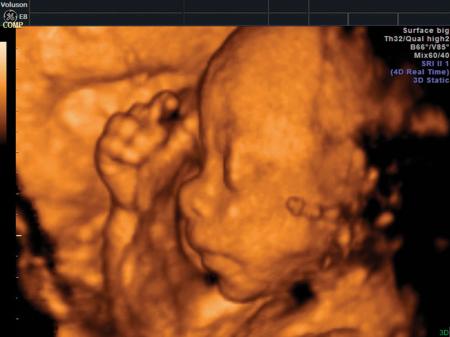

Fotografías de ecografías 4D HD/5D

Haga click sobre las imágenes para ampliar